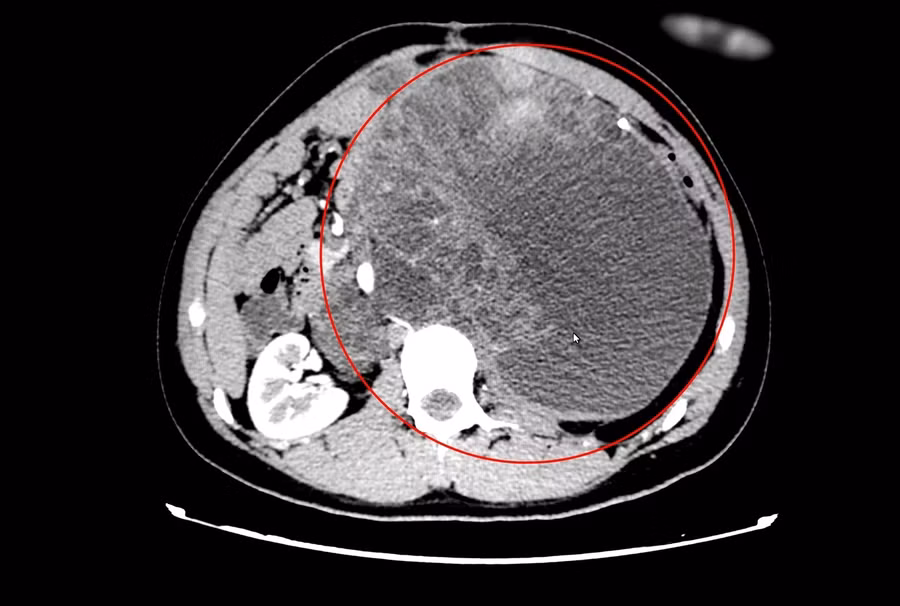

Theo thông tin từ Bệnh viện Đa khoa tỉnh Quảng Ninh cho biết, bệnh nhân được chẩn đoán có u gồm nhiều khối hỗn hợp đặc và lỏng dính nhau, bao bọc xung quanh động mạch, tĩnh mạch chủ bụng và các động mạch vùng chậu. Khối u kích thước lớn 20x30 cm, chèn ép và xâm lấn vào thận trái gây mất chức năng.

Kết thúc 4 đợt truyền thuốc, khối u di căn trong bụng ngày càng to chiếm hết ổ bụng, chèn ép thận bên trái gây mất chức năng.

Ngày 4/4/2021, bệnh nhân được nhập viện Bệnh viện Đa khoa tỉnh Quảng Ninh, chụp cắt lớp toàn thân, nội soi tiêu hoá cũng như làm các xét nghiệm để đánh giá giai đoạn bệnh và tình trạng sức khoẻ hiện tại.